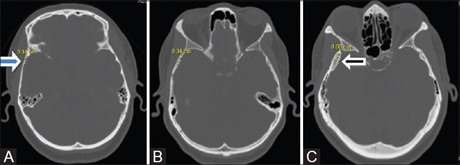

Unusual sites of intracranial metastases from renal cell carcinoma presenting only with neurological symptoms

Dr. Puneet Garg, Hira Lal, Swapndeep Atwal, Suparva Nayak, Alok K Udiya (Author)

132-135